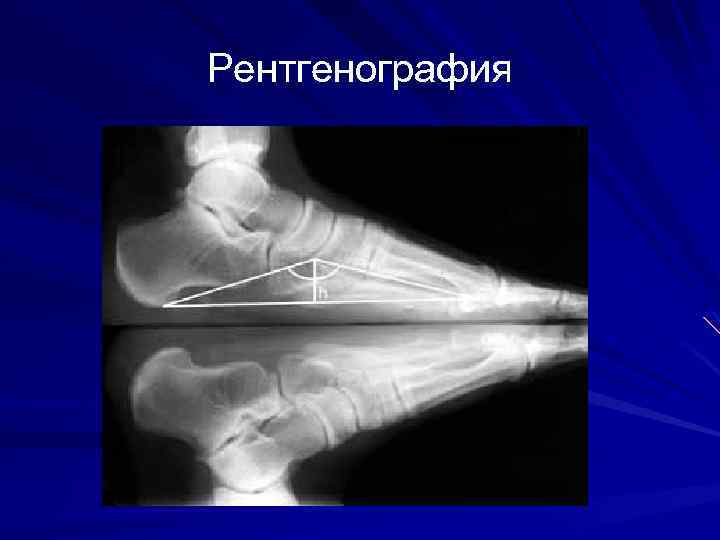

Рентгенография

Рентгенография выполняют на специальной подставке в условиях естественной статической нагрузки (при двуопорном стоянии обследуемого) на R-грамме стопы в боковой проекции измеряют высоту и угол продольного свода стопы (ладьевидный угол свода) с 8 лет, когда уже сформироваласть и четко контурируется на R-грамме ладьевидная кость

Рентгенография В норме ладьевидный угол свода составляет 125°, высота продольного свода - 39 -40 мм, вальгусное положение заднего отдела стопы 5 -7°. У детей дошкольного возраста высота продольного свода стопы в норме может колебаться от 19 до 24 мм.

Степени плоскостопия При лёгкой степени плоскостопия отмечают снижение высоты продольного свода стопы до 1520 мм, уменьшение угла высоты свода до 140°, вальгусное положение заднего отдела - до 10°, отведение переднего отдела стопы — в пределах 8 -10°.

Степени плоскостопия Средняя степень плоскостопия характеризуется снижением свода стопы до 10 мм, уменьшением высоты свода до 150160° с вальгусным положением заднего отдела и отведением переднего до 15°.

Степени плоскостопия Тяжёлая степень плоскостопия сопровождается снижением свода стопы до 0 -5 мм, уменьшением угла высоты свода стопы до 160180°, вальгусным положением заднего отдела и отведением переднего более 20°. При тяжёлой степени деформация ригидная, коррекции не поддаётся.